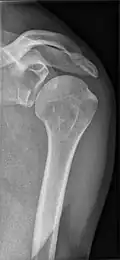

Skapulahalsbruch

Skapulahalsbrüche müssen bei deutlicher Verschiebung oder Verkippung des Glenoids ebenfalls operativ reponiert und fixiert werden. Durch den Zug der langen Sehne des Musculus triceps brachii rutscht das Glenoid oft nach unten (kaudal) und verkippt. Bei Skapulahalsbrüchen besteht zudem die erhöhte Gefahr einer Verletzung des durch die nahe Incisura scapulae verlaufenden Nervus suprascapularis, die nur im Elektromyogramm nachweisbar ist.